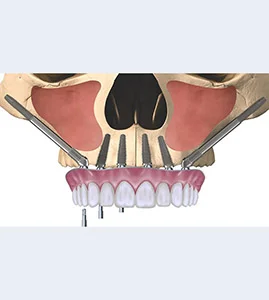

Specialized in Corticobasal Implantology, single day implant placement is now possible in Bangalore, exclusively at Vijaya Dental International. We have 3 branches in Bangalore.

Restore your smile with our All-on-6/8 Dental Implants..

At Vijaya Dental International, we specialize in providing advanced Same-Day Implants and Tooth Replacement solutions, offering fast, effective options for missing teeth. Our team of dental implant experts uses state-of-the-art technology to ensure that you can walk out with a fully functional, natural-looking smile on the same day. Whether you’ve lost a single tooth or need a full arch restoration, our personalized approach guarantees comfort, precision, and long-lasting results. Let us help you restore your confidence and smile with our expert implant and tooth replacement services.